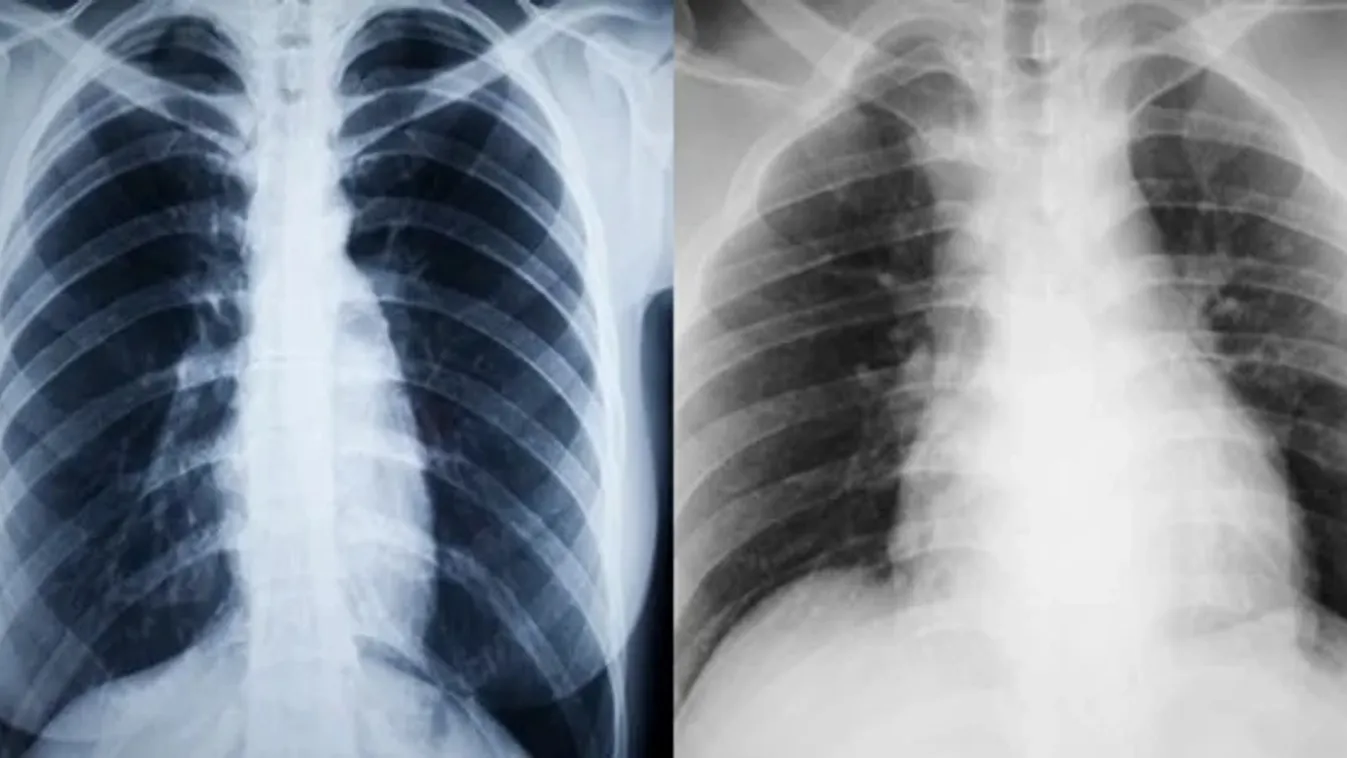

KÜLFÖLD 2021. 02. 22. Véletlenül egy koronavírusos donor tüdejét ültették be, a páciens belehalt a fertőzésbe Az Egyesült Államokban ez az első bizonyított eset, amikor szervtranszplantáció útján terjedt emberről emberre a koronavírus.